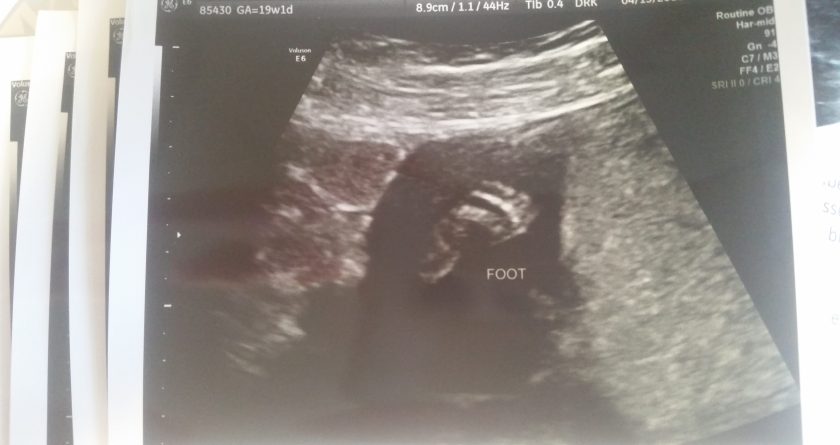

When we entered 2016, I can honestly say I was the happiest I had been in my life. I was pregnant with our first child. I was going to be a mother and Andy was going to be a father. By Christmas, Andy and I would be a family of three with a beautiful baby. I was on top of the world; the prospects of the Year 2016 held unlimited happiness for us.

It was around 20 weeks that we found out our son had Down syndrome (Ds). I will be honest with you. Our first reaction was that of devastation. And of grief. (I am shaking my head. Yes, grief). We felt like our world had come crashing down on us. The future we were counting on was no longer the future we were going to get.

Unfortunately, with Ds comes an increased risk in medical issues. We learned early on that Jensen had a confirmed heart defect (VSD) and another potential heart defect (it turns out he had a total of 4). And after 30 weeks, unbeknownst to all of us, he very quickly developed fluid around his lungs and stomach (hydrops fetalis).